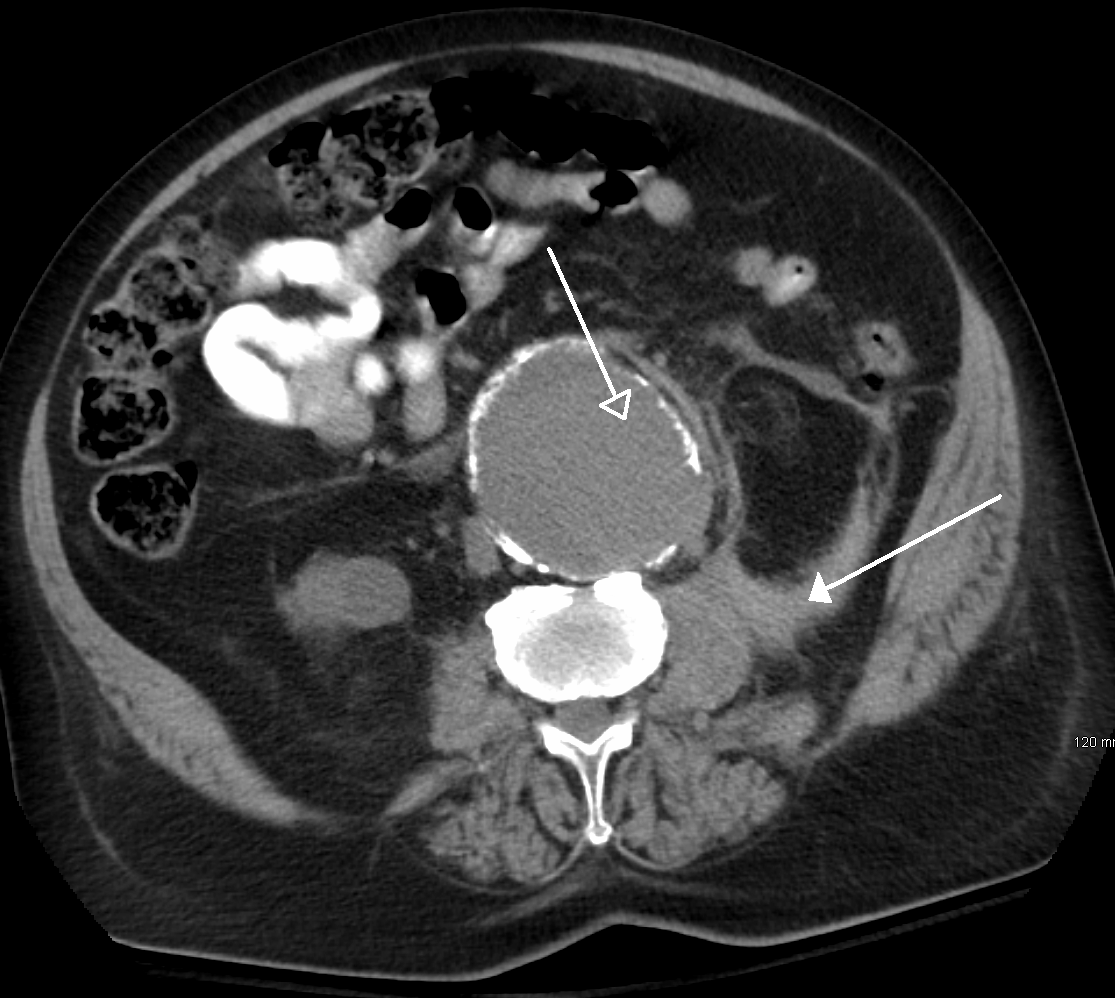

복부대동맥류는 일반적으로 신체 검사, 복부 초음파 검사, CT 스캔으로 진단된다. 단순 복부 방사선 사진은 대동맥벽이 석회화된 경우 대동맥류의 윤곽을 보여줄 수 있지만, 전체 대동맥류의 절반 미만에서만 확인 가능하다.복부 초음파 검사는 대동맥류를 선별하고, 대동맥류가 있는 경우 그 크기를 결정하는 데 사용된다. 또한, 복강 내 자유 액체도 감지할 수 있다. 이는 비침습적이고 민감하지만, 장내 가스나 비만은 유용성을 제한할 수 있다.[29] CT 스캔은 대동맥류에 대해 거의 100%의 민감도를 가지며, 해부학적 구조와 혈관 내 복구 가능성을 상세히 설명하여 수술 전 계획에도 유용하다. 파열이 의심되는 경우, 후복막강 내 체액도 신뢰할 수 있게 감지할 수 있다. 대동맥류를 시각화하는 데 덜 사용되는 대체 방법으로는 MRI와 혈관조영술이 있다.[30]

복부 대동맥류는 일반적으로 신체 검사, 초음파 또는 CT 스캔으로 진단된다. 복부 방사선 사진은 동맥벽이 경화되었을 때 동맥류의 윤곽을 보여주지만, 동맥류 절반 이하에서만 확인 가능하다. 초음파 검사는 동맥류 검사 및 동맥벽 크기 결정에 사용되며, 자유 복막액이 검출될 수 있다. 하지만 장내 가스나 비만은 검출을 어렵게 할 수 있다. CT 스캔은 동맥류에 대해 거의 100% 확신을 가지기 때문에 수술 전 계획에 유용하며, 파열이 의심되는 경우 복막 후방 액체를 확실하게 감지할 수 있다. MRI 및 혈관 조영술도 사용 가능하지만, 자주 사용되지는 않는다.[119]